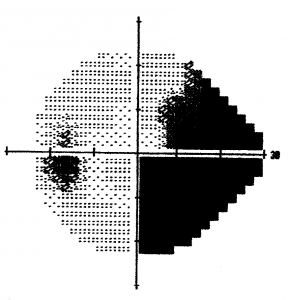

Visual Field Analysis

The visual field test is a subjective measure of central and peripheral vision and is used to diagnose, determine the severity of, and monitor glaucoma. It evaluates vision loss due to glaucoma, damage to the visual pathways of the brain, and other optic nerve diseases. When glaucoma is diagnosed the visual field data is used to determine the severity of disease. This staging information is useful in choosing a target intraocular pressure and determining follow-up.